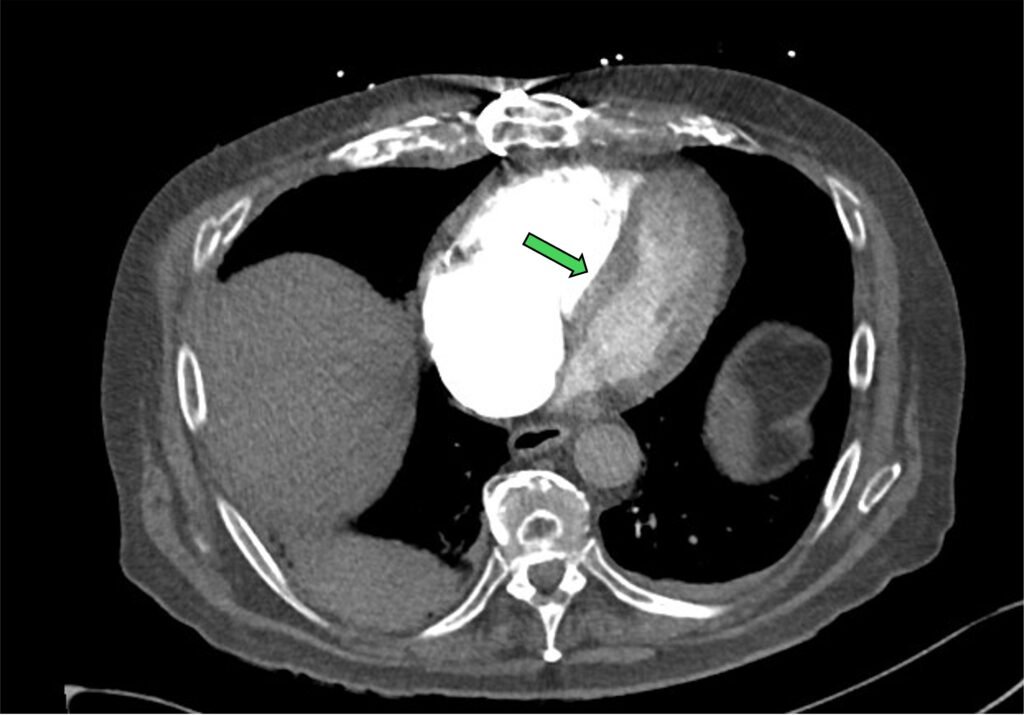

Sometimes the formation of clots is so extensive, you can see a saddle shape clot within the bifurcation of the pulmonary trunk. This (saddle PE) is often associated with high clot burden and RV strain.

Figure 6: saddle PE (green arrow)